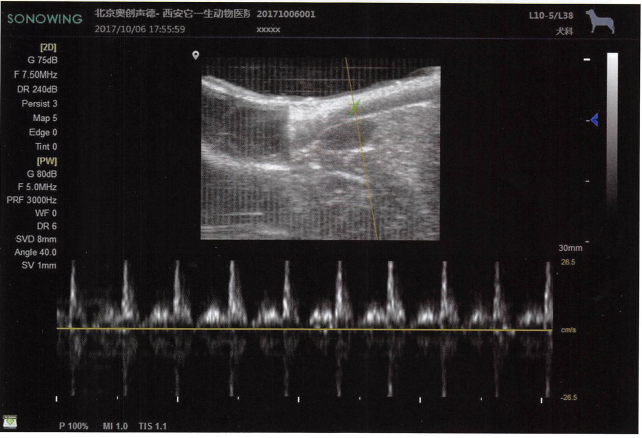

7.超声造影,震荡的生理盐水输液,微气泡使血液显影。